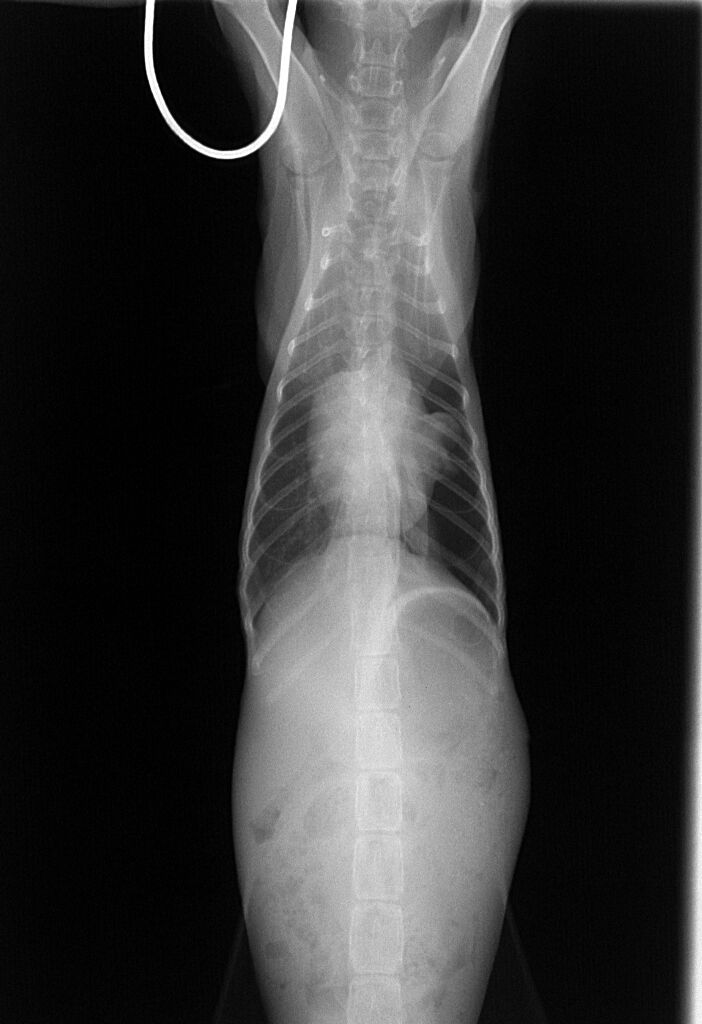

食欲はありませんでしたが、ICU内にて点滴と酸素供給を続け1日、2日と経つうちに徐々に起きている時間が長くなり、3日後には、ICUから出ても呼吸は安定し、食欲が出てきました。7日後にはほぼ正常になり、フードもよく食べて体重もどんどん増えてきました。そこで、レントゲンを撮り、その結果が下の写真です。

押しつぶされて小さくなっていた左の肺はきれいに全体に広がっているのがわかります。これでもう安心できる状態でした。その後、1週間くらい入院して、退院後、先住の他の猫ちゃんとも仲良く、家族のみなさんに大切に育てられています。